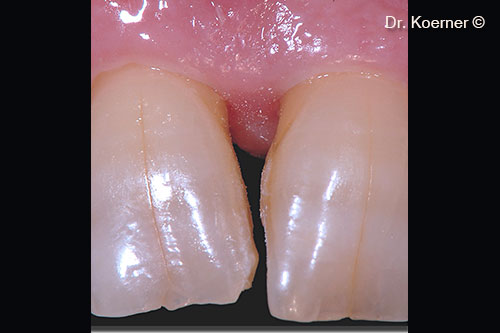

Bệnh nhân nam (61 tuổi) có tổn thương nha chu ở vùng thẩm mỹ.

Khuyết tật nha chu khu trú 11

Súng ngắn bỏ túi 9mm